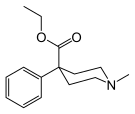

Structures

Prodines

- Allylprodine

- (α/β)-Meprodine

- Desmethylprodine (MPPP)

- PEPAP

- (α/β)-Prodine

- Prosidol

- Trimeperidine (promedol)

Structures